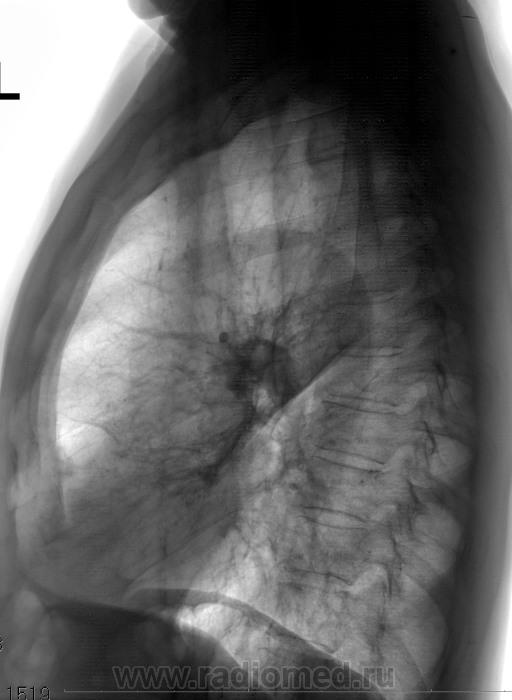

Пока пневмония в верхней доле, перисциссурит

Красный может оказаться вовсе не головкой корня (как-то его больно "латералит" от центра), желтый может оказаться обструктивным пневмонитом язычкового сегмента, зеленый - не просто пневмонитом S2 c перициссуритом, но и с костальным выпотом. Полисегментарность изменений и их сближенность к центру, к корню наводят на мысль о центральном онко. (Да и просвет левого главного бронха на боковом снимке чем-то прикрыт).

В S 2 динамика положительная, а вот язычковые сегменты настораживают ( эндобронхиальное образование ?). Резать будете или есть возможность бронхаскопию выполнить? Впрочем, пациент хроник. Можно с архива начать.

Динамика положительная в двойке, а в язычках, считаю, отрицательная. Можно, кончено, и полечить. Но и  разбираться с причиной гиповентиляции  надо.